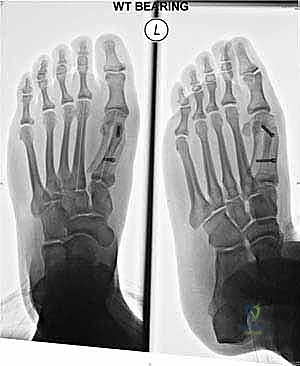

Before we even consider making an incision, our blueprint for this procedure begins with meticulous preoperative planning. We've thoroughly evaluated the patient's weight-bearing anteroposterior (AP) and lateral radiographs of the foot. These images are critical for assessing several key parameters:

- Intermetatarsal Angle (IMA): The primary indication for a Scarf osteotomy is typically a symptomatic hallux valgus with an IMA of less than 20 degrees. We're looking for a stable first metatarsocuneiform joint here; instability might push us towards a fusion.

- Hallux Valgus Angle (HVA): This measures the lateral deviation of the great toe.

- Distal Metatarsal Articular Angle (DMAA): This assesses the orientation of the articular surface of the first metatarsal head. An abnormal DMAA, especially in juvenile hallux valgus, can be corrected effectively with a Scarf.

- Sesamoid Position: The position and condition of the sesamoids under the first metatarsal head. Lateral subluxation is a hallmark of hallux valgus, and their reduction is a key indicator of successful correction.

Today's patient presents with symptomatic hallux valgus, an IMA of 16 degrees, and moderate lateral sesamoid subluxation, making the Scarf osteotomy an ideal choice.

c. Final Radiographic Assessment:

Before closing, we perform a final radiographic assessment using image intensification. We take AP, oblique, and lateral views of the foot, ensuring the foot is flat on the image intensifier plate, mimicking a weight-bearing position.

We meticulously check for:

* Reduction of the Intermetatarsal Angle (IMA): Ensure adequate correction.

* Screw Position and Length: Confirm no intra-articular penetration and good bone purchase.

* Relocation of the Sesamoids: Verify they are centered beneath the metatarsal head.

* Overall Alignment: Assess the hallux valgus angle and distal metatarsal articular angle.

At this point, if the hallux valgus angle remains elevated despite adequate first metatarsal correction, we reassess the need for a concurrent proximal phalangeal osteotomy (Akin osteotomy). This is a distal closing wedge osteotomy of the proximal phalanx, fixed with a small staple or K-wire, to further correct the hallux position.